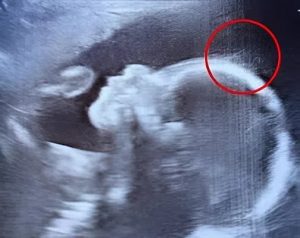

« Un instant… est-ce que ce serait… des cheveux ? », s’exclame-t-il, visiblement étonné et ravi. Un collègue rejoint la salle, observe l’écran et lance une blague sur une rockeuse en herbe. À l’image, de légers filaments semblent danser avec grâce, évoquant une chevelure déjà bien présente. Un spectacle aussi rare que poétique.

L’équipe médicale rassure immédiatement la future maman : il est tout à fait normal que la pousse capillaire débute in utero. Ce qui sort de l’ordinaire, en revanche, c’est la clarté avec laquelle cette chevelure est visible à l’écran à ce stade de la grossesse, témoignant d’une longueur tout à fait inhabituelle.